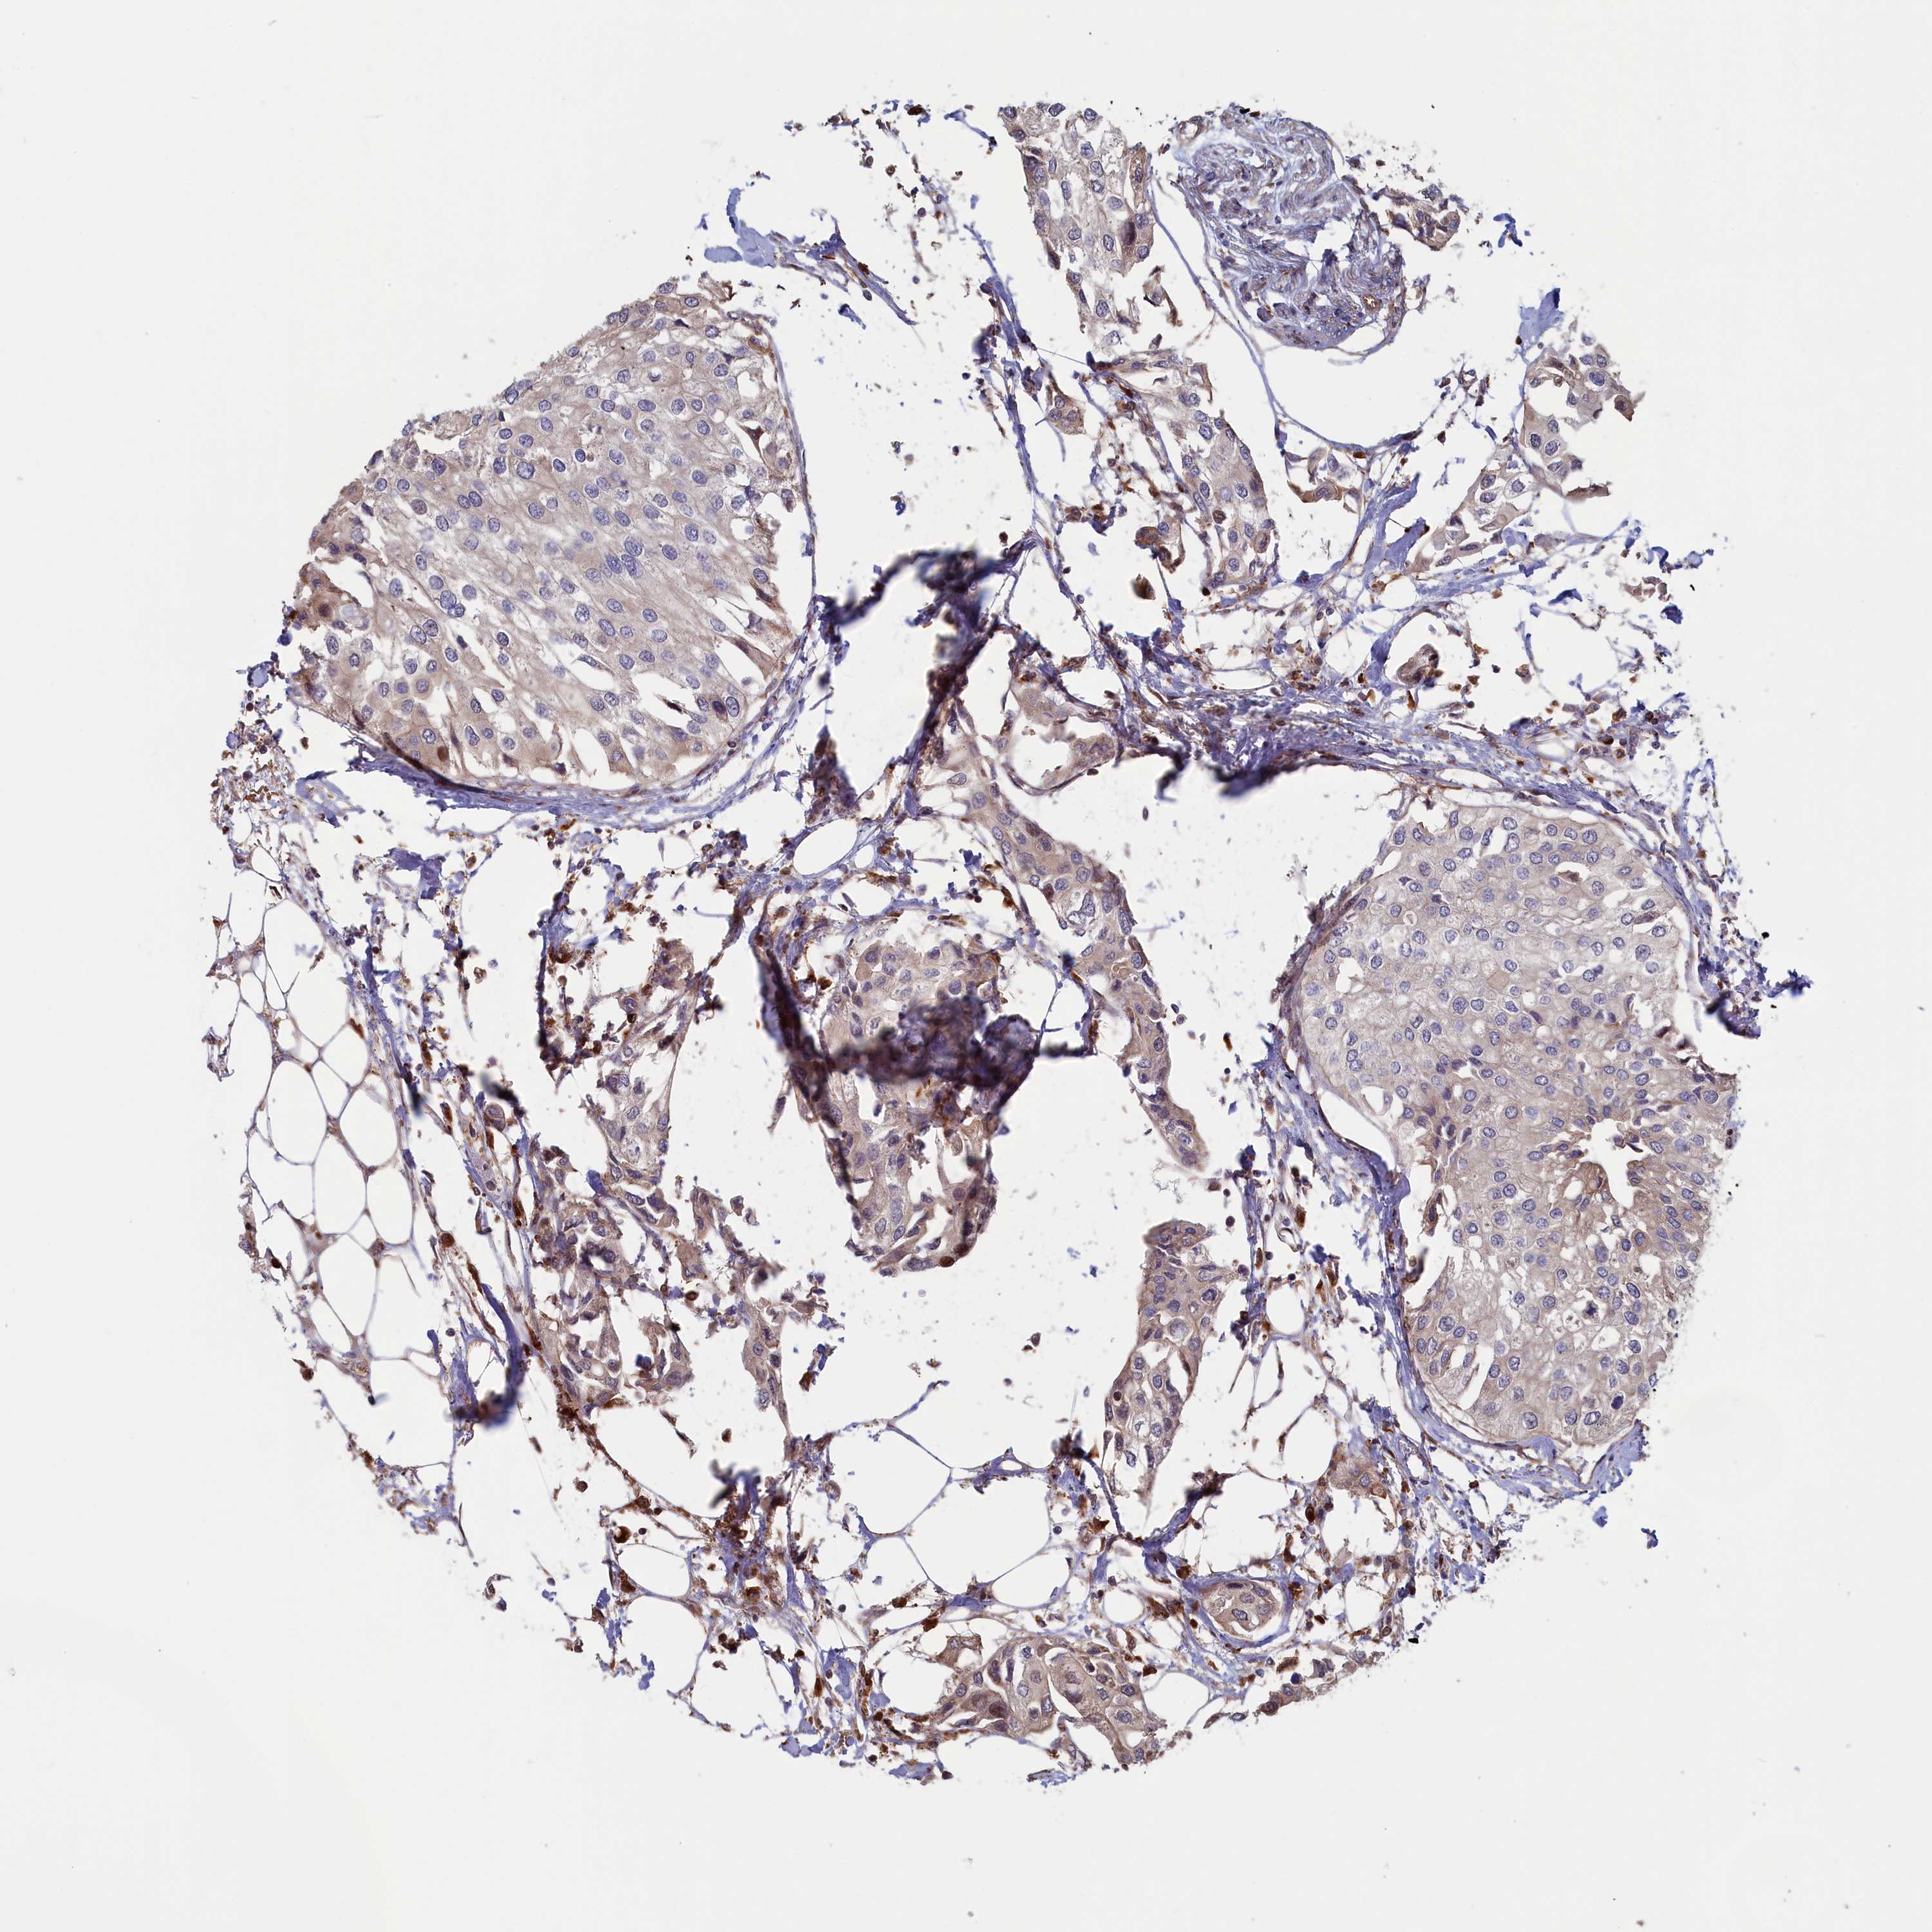

UROTHELIAL CANCER - Protein expressioni

A mouse-over function shows sample information and annotation data. Click on an image to view it in a full screen mode. Samples can be filtered based on level of antibody staining by selecting one or several of the following categories: high, medium, low and not detected. The assay and annotation is described here.

Note that samples used for immunohistochemistry by the Human Protein Atlas do not correspond to samples in the TCGA dataset.

Antibody stainingi

Antibody staining in the annotated cell types in the current human tissue is reported as not detected, low, medium, or high, based on conventional immunohistochemistry profiling in selected tissues. This score is based on the combination of the staining intensity and fraction of stained cells.

Each image is clickable and will lead to virtual microscopy that enables deeper exploration of all samples and also displays staining intensity scores, fraction scores and subcellular localization as well as patient and tissue information for each sample.

Antibody HPA041314

Staining

High

Medium

Low

Not detected

Intensity

Strong

Moderate

Weak

Negative

Quantity

>75%

75%-25%

<25%

None

Location

Nuclear

Cytoplasmic/membranous

Cytoplasmic/membranous,nuclear

Urothelial carcinoma, High grade

Urothelial carcinoma, Low grade